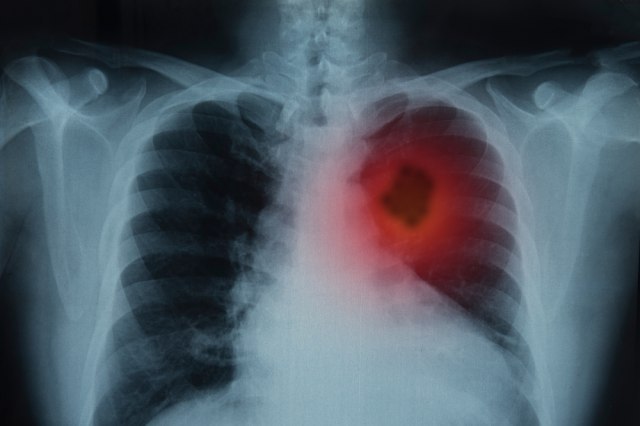

Od njega godišnje umre 4.500 Srba: Rak pluća u ranom stadijumu može otkriti novi test krvi

Rak pluća je najsmrtonosniji oblik karcinoma, a jedan od razloga je i činjenica da se ovaj zloćudni tumor uglavnom otkriva u uznapredovalim fazama bolesti. Od ove teške bolesti u Srbiji svake godine oboli više od pet hiljada ljudi, a 75 odsto pacijenata premine. Stručnjaci se nadaju da bi bolest mogla što pre da se otkrije i leči, kako bi se poboljšalo preživljavanje pacijenata. Novu nadu budi test krvi koji bi mogao da dijagnostikuje rak pluća u početnoj fazi bolesti.

Karcinom pluća je vodeći uzrok smrti od raka u svetu. Lekari kažu da petogodišnje preživljavanje pacijenta zavisi od oblika i stadijuma karcinoma i od toga da li je došlo do širenja malignih promena na druge organe tela. Bitno je, pre svega, bolest otkriti na vreme kako bi pacijent što hitnije dobio najbolju moguću terapiju.

Rak pluća se često dijagnostikuje u napredovalim stadijumima bolesti. Istraživanja navode da veliki broj pacijenata u početnim fazama bolesti nema jasne simptome koji bi mogli da upute da se radi o karcinomu pluća.